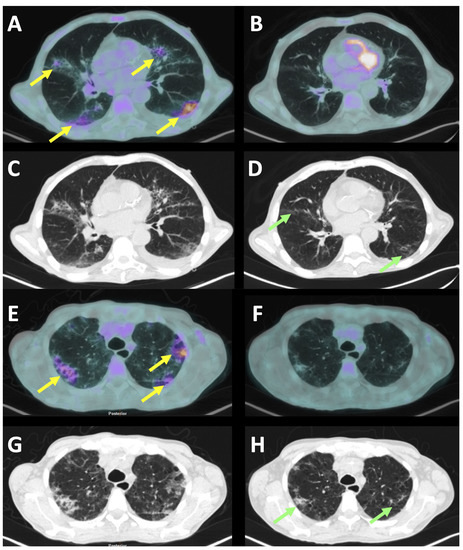

The basal PET/CT showed a pathologic uptake in the upper-diaphragmatic lymph nodes (the neck, mediastinum, and supraclavicular regions) and an increased spleen volume with a normal hepato-splenic metabolic gradient. The lower-diaphragmatic lymph nodes, detected by the CT scan, were not characterized by an increased [18F]FDG uptake. In both lungs, an increased and diffused [18F]FDG uptake was observed, corresponding to the ground glass opacities at the CT scan and, in particular, in both posterior-basal regions of the lungs (Figure 1A–D). Two weeks after the Tocilizumab, a PET/CT showed a modest improvement of both the haematological and chest diseases, with a persisting residual [18F]FDG uptake of lower intensity, compared to that of the basal study, in both lungs and the upper-diaphragmatic lymph nodes.

Figure 1.

Axial section of the [18F]FDG-PET/CT scan of patient A (A–D) and patient B (E–H) before the Tocilizumab infusion (left images) and 14 days after therapy (right images). Yellow arrows indicate the areas of interstitial pneumonia that were metabolically active at the FDG-PET. After therapy, despite the FDG-PET being completely negative, there were still some areas of ground-glass at the CT scan (green arrows). Indeed, the normalization of the CT scan always occurred later than the normalization of the FDG-PET, thus highlighting the importance of monitoring patients’ therapy by FDG-PET.

The basal PET/CT showed a pathologic uptake in many of the lymph nodes of the upper- and lower-diaphragmatic stations (the neck, mediastinum, left axillary region, supraclavicular regions, para-esophageal site, celiac, peri-gastric curvature, in the para-aortic area, inter-portal-cava region, and at the hepatic hilum) and an increased spleen volume with an inversion of the hepato-splenic metabolic gradient. In both lungs, a slightly increased and diffused [18F]FDG uptake was observed, corresponding to the ground glass opacities at the CT scan and, in particular, in both the posterior-basal regions of the lungs (Figure 1E–H).

A follow-up study after the Tocilizumab showed a progression of the haematologic disease and complete normalization of the [18F]FDG uptake in the lungs.